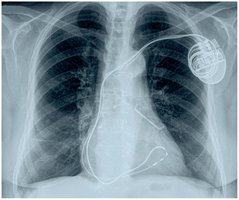

Pacemaker Implantation

A pacemaker is an electronic device implanted to regulate heart rhythm.